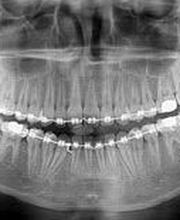

Presso lo studio del Dott. Daniele Franco Cardaropoli, mettiamo al centro la salute del tuo sorriso con tecnologie d'avanguardia. Grazie all'utilizzo del LASER odontoiatrico, offriamo trattamenti più rapidi, meno invasivi e con tempi di guarigione ridotti: il massimo del comfort per ogni paziente. Dalla prevenzione orale allestetica, il nostro team di medici chirurghi e odontoiatri copre ogni necessità: * Chirurgia e Implantologia: Soluzioni fisse e mini-invasive. * Estetica e Igiene: Sbiancamento professionale e pulizia dentale profonda. * Cure Specialistiche: Endodonzia, parodontologia e protesi. * Pedodonzia: Un dentista dedicato ai più piccoli per farli crescere col sorriso. Affidati a mani esperte per la cura dei tuoi denti. Qualità, innovazione e delicatezza in un unico studio.